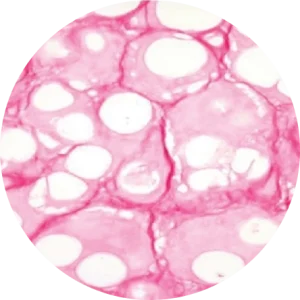

image_progress-of-collagen-reproduction_02

image_progress-of-collagen-reproduction_01

image_progress-of-collagen-reproduction_03